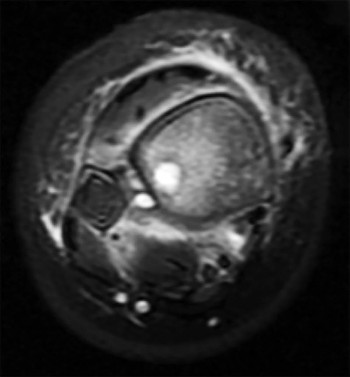

An 8-year-old Japanese girl presents with a painless, palpable 'clunk' on the lateral side of her left knee during terminal extension. MRI confirms a discoid lateral meniscus. Which specific variant of a discoid meniscus is characterized by an absent posterior meniscotibial attachment, leading to hypermobility and snapping?